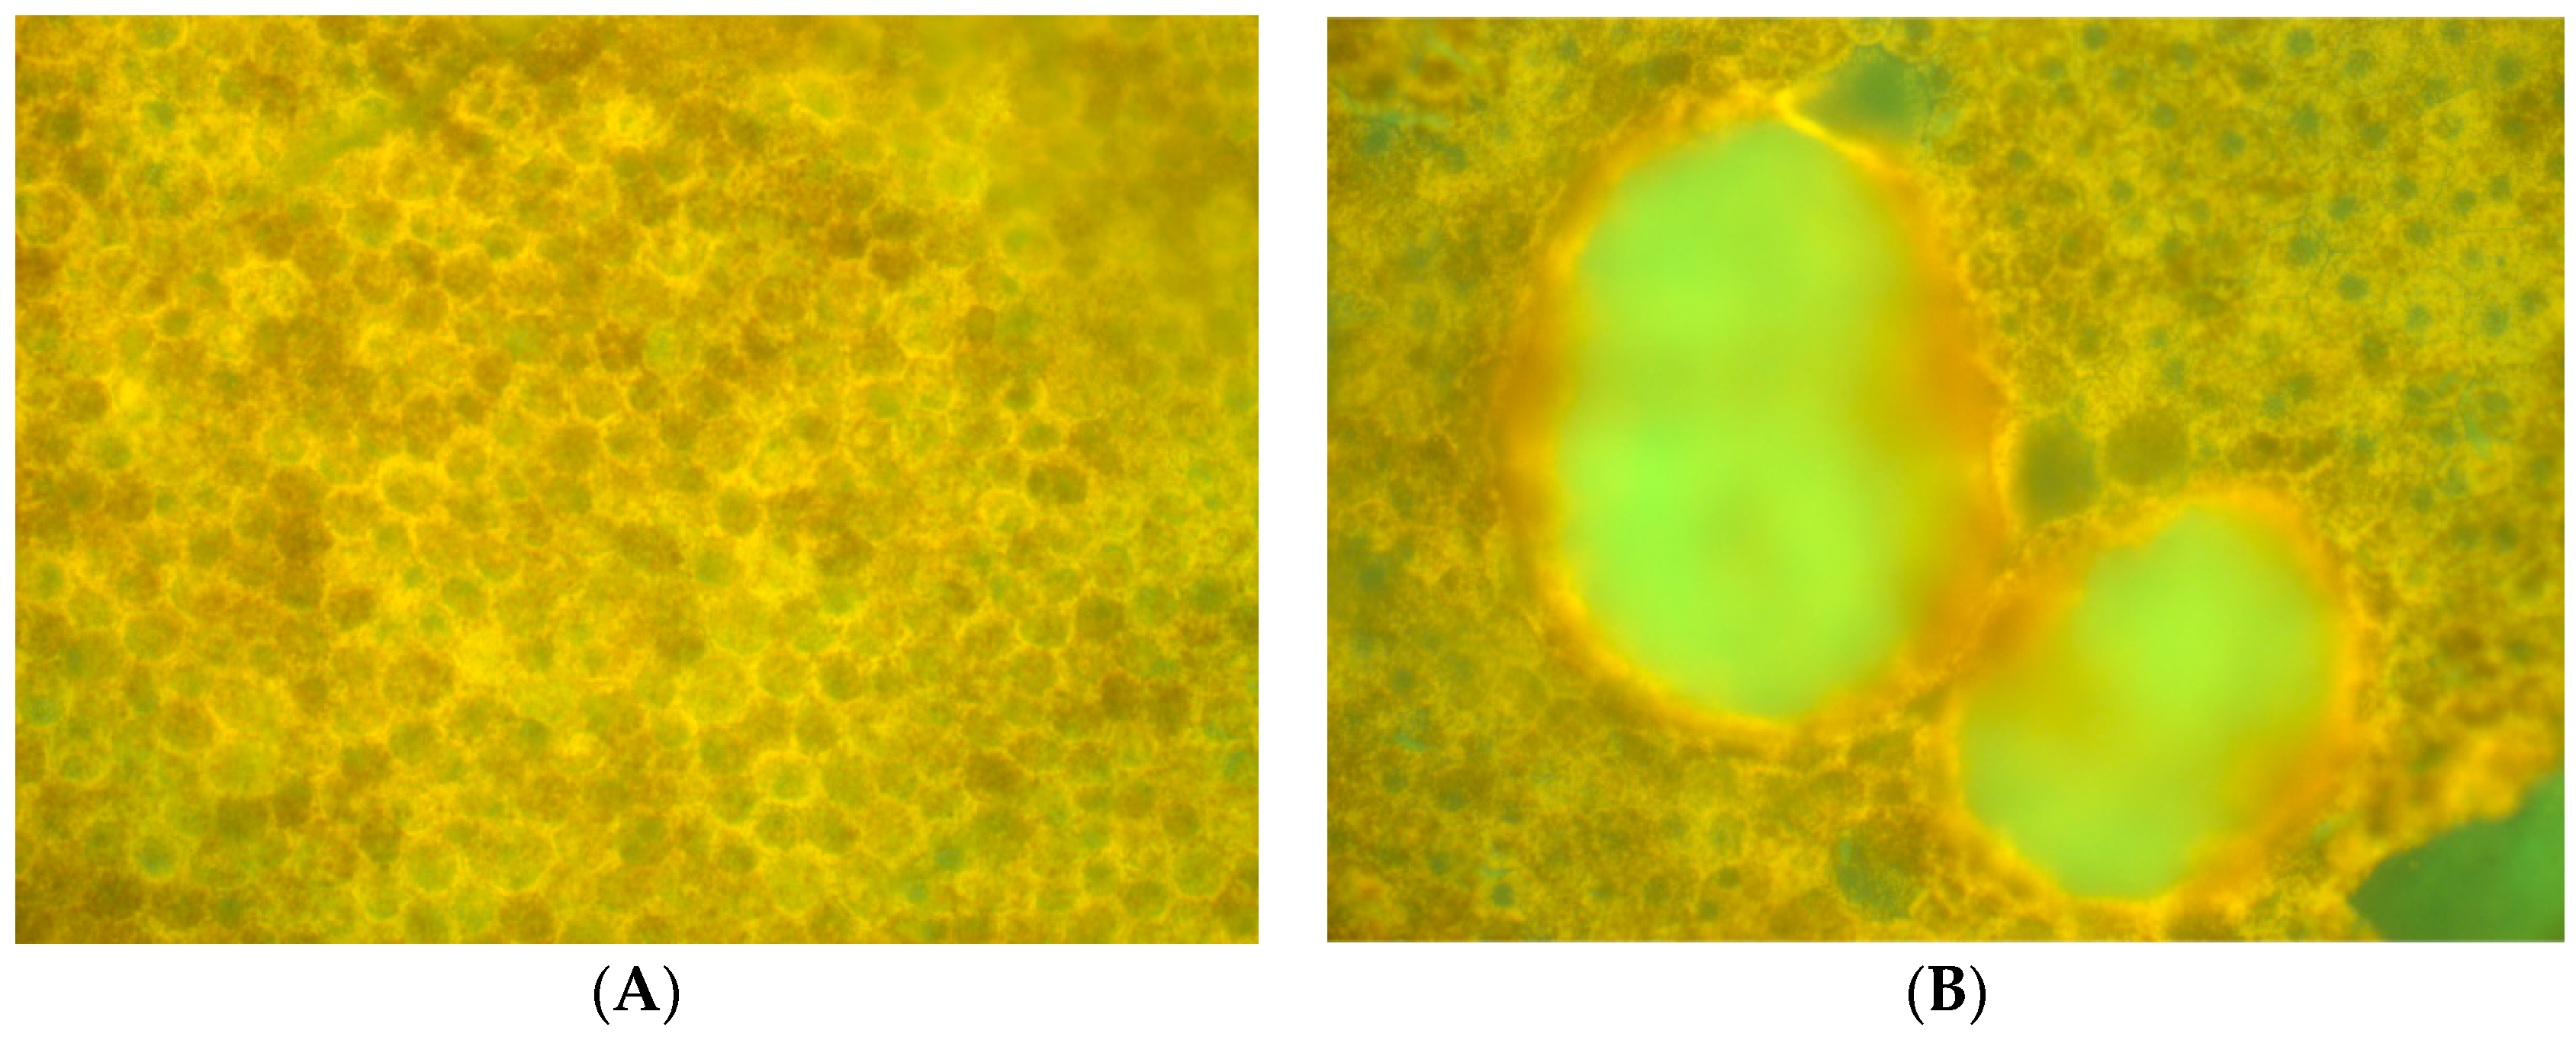

The same fluorophore families were recovered as previously described [14], that is, three spectra (S1, S2, and S3), with S1, S2 attributable to RPE LF and S3 attributable to RPE MLF and one spectrum (SDr) attributable to drusen and sub-RPE diffuse deposits. However, adding a third excitation appeared to improve the spatial and spectral recovery of the NMF algorithm. Spatially, abundance images seemed to suggest more information about fluorophore localizations within drusen deposits. In one tissue (Figure 1B) with drusen analyzed with two excitation wavelengths (Figure 2A,C and Figure 4B), the fluorophore source of S1 overlapping with drusen (i.e., sharing the same x, y but not necessarily the same z) [14] appeared to be attenuated, possibly due to out-of-plane RPE cells overlying the druse. When this tissue was analyzed with three excitation wavelengths (Figure 2B,D and Figure 4D), a more detailed, consistent pattern emerged. Spectrally, the recovered waveforms appeared less noisy, with better-defined peaks, than our previously reported with two excitation wavelengths. In a tissue without AMD and without drusen (Figure 1A), the spectral recovery and abundance images were similar with analogous peaks and spectra were recovered using both two (Figure 3A,C and Figure 4A) and three excitation wavelengths (Figure 3B,D and Figure 4C).

Figure 1. Unprocessed autofluorescence (AF) flatmount emission of normal and age related macular degeneration (AMD) eyes cited at 436 nm. (A) An example normal sample without AMD or any drusen. (B) An example AMD sample with two large drusen centrally in the image.